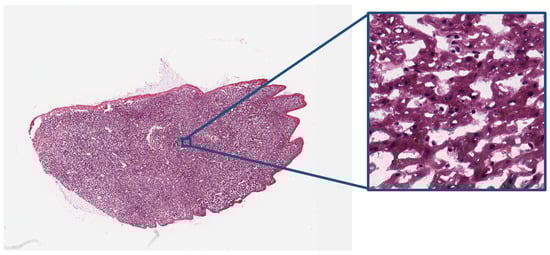

2.5. Digital Pathology

| - | H&E Stained Digital Pathology | (6000, 6000, -) | 24 bits (color) |